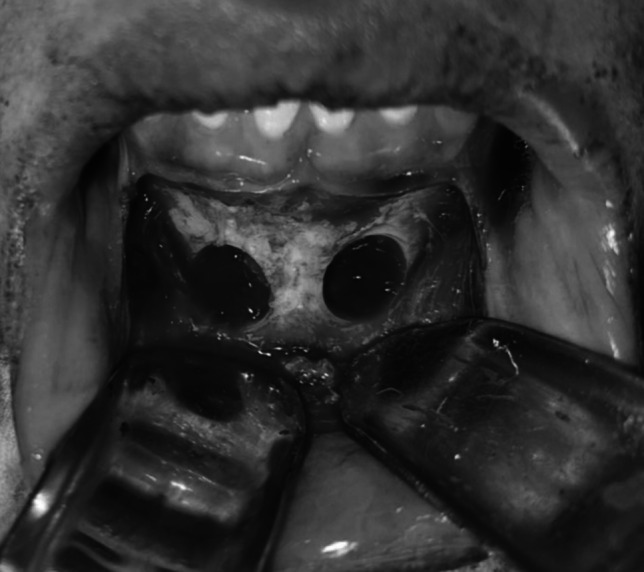

有许多因素可以影响下颌缺陷的矫正和特定移植材料的成功,包括上颌和下颌骨的组织学和密度以及移植材料本身。本研究比较了使用混合可注射富血小板纤维蛋白(i-PRF)或异种移植物的下颌联合嵌骨移植增强前上颌水平牙槽嵴的临床结果。将12例成人上颌牙槽嵴水平缺损患者随机分为两组,每组6例。I组采用下颌联合嵌骨移植物混合I - prf, II组采用下颌联合嵌骨移植物混合异种移植物(InterOss有机松质颗粒)。术前和随访6个月时采用CBCT扫描测量牙槽嵴宽度和骨密度。两组牙槽嵴宽度和骨密度均有改善。6个月后测量骨宽度和骨密度的增加,II组显著大于I组(p = 0.040)。水平牙槽嵴增强术采用嵌板下巴移植物结合异种移植物是成功的,并提供了足够的骨数量和质量。

There are numerous factors that can impact both the correction of jaw deficiencies and the success of a particular grafting material, including the histology and density of both the maxillary and mandibular bones and the grafting material itself. This study compares the clinical outcomes of grafted augmentations of the horizontal alveolar ridge of the anterior maxilla using mandibular symphysis onlay bone that was admixed with either injectable platelet-rich fibrin (i-PRF) or xenografts. Twelve adult patients with horizontal maxillary alveolar ridge deficiency were randomly divided into two groups of six patients each. Group I received mandibular symphysis onlay bone grafts mixed with i-PRF, while Group II received mandibular symphysis onlay bone grafts admixed with xenografts (InterOss anorganic cancellous granules). CBCT scans were used to measure alveolar ridge width and bone density both preoperatively and at 6-month follow-up. Both groups showed improvements in alveolar ridge width and bone density. The increase in measured bone width and density after 6 months in Group II was significantly greater than that in Group I (p = 0.040). Horizontal alveolar ridge augmentation using an onlay chin graft in combination with xenografts was successful and offered adequate bone quantity and quality.